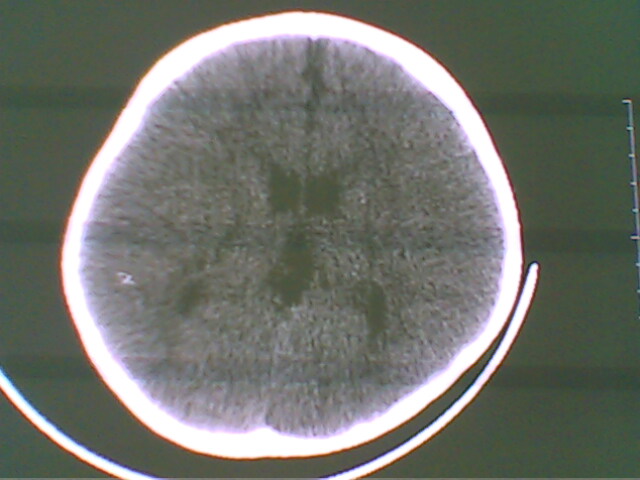

未见明显异常

未见异常

未见明显异常。

无异常发现.

图像有点差,未见明显异常。

正常.

未见明确异常。

图像稍稍有点差,未见明显异常。